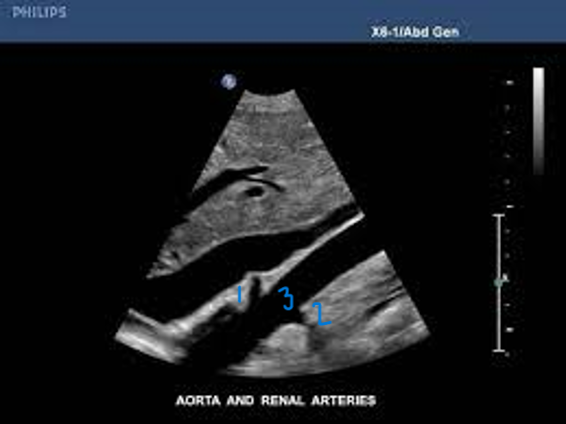

<p>In this Sagittal-Coronal plane, what is #1?</p>

In this Sagittal-Coronal plane, what is #1?

Right Renal Artery

<p>In this Sagittal-Coronal plane, what is #2?</p>

In this Sagittal-Coronal plane, what is #2?

Left Renal Artery

<p>In this Sagittal-Coronal plane, what is #3?</p>

In this Sagittal-Coronal plane, what is #3?

Aorta

<p>What number is known as the RRA</p>

What number is known as the RRA

#3